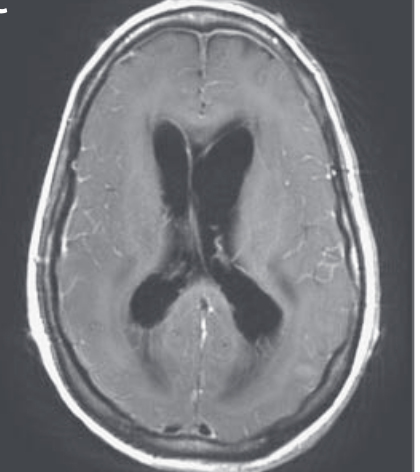

DDx for meningoencephalitis w/ mononuclear pleocytosis, inc opening pressure, normal glucose & inc protein. MRI diffuse pachymeningeal & leptomeningeal enhancement, sulcal hyperintensity in basal cisterns & cerebellum on T2, +hydrocephalus & no improvement on acyclovir and abx

Among >50 serotypes of adenovirus, serotype 2 is most common serotype w/ meningoencephalitis & disseminated disease. Published reports of neuropathological features are scarce but show b/l sometimes symmetric, necrotizing lesions w/ striking predilection temp lobe/ventricles